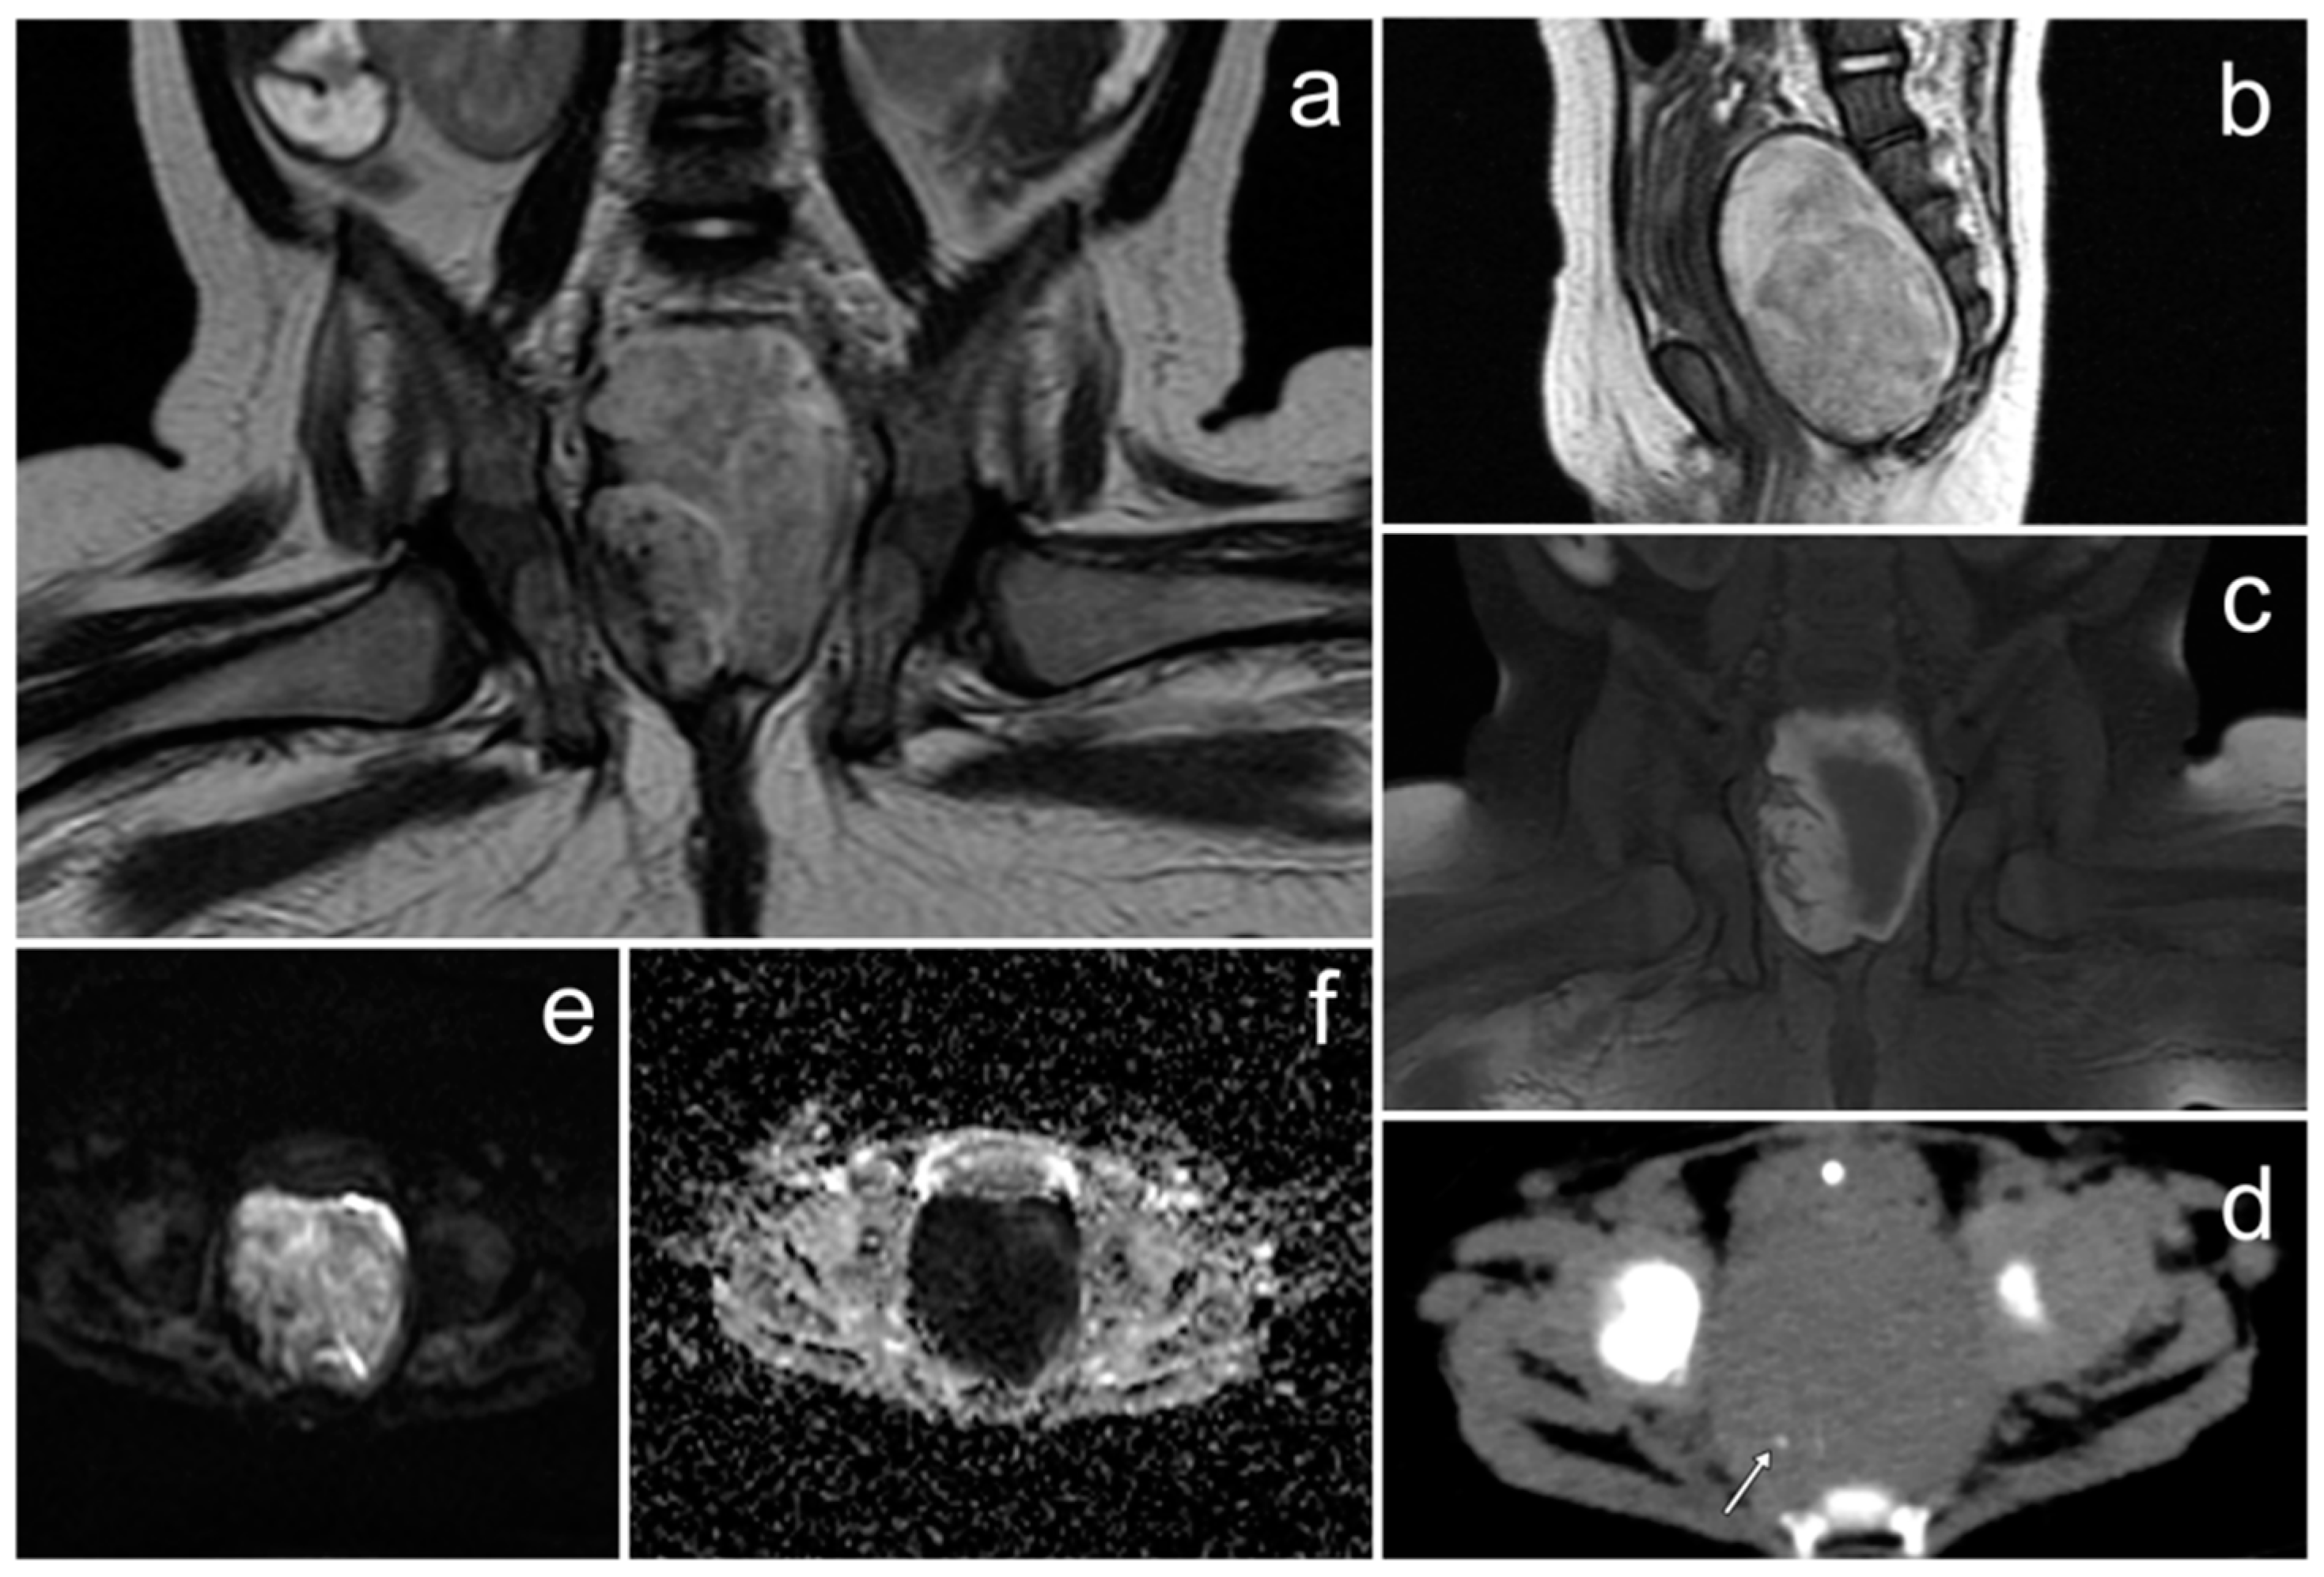

3.3. Diffuse Large B-Cell Lymphoma of the Ovaries

Case Report

| Diffuse large B-cell lymphoma of the ovaries | bilateral, homogenous solid masses; “touching” large ovaries, small cysts arranged linearly around the periphery | elevated Ca-125 andLDH levels | non-specific; pain or discomfort in the abdominal cavity, enlarged abdominal circumference, irregular bleeding, B symptoms (fever, night sweats, or weight loss) |